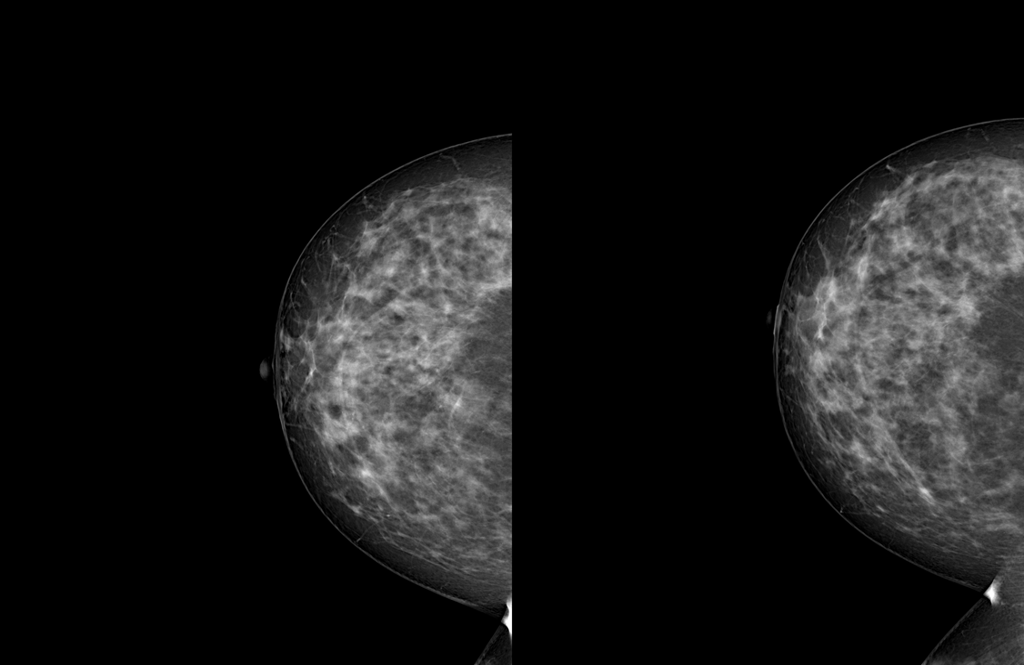

Refer to caption

(a) L-CC projection

(b) L-MLO projection

Figure 6: Registration results for an example pair in the L-CC and L-MLO projections. The overlays show the fixed image (in blue) and the moved image (in yellow) after registration using different methods: unregistered, Affine, SyN, Curvilinear Coordinates, IDIR, VoxelMorph, TransMorph, and MammoRegNet. Successful alignment is indicated by the overlap of corresponding anatomical structures in white.

The quantitative evaluation of all registration methods on the MGRegBench benchmark is presented in Table 1, with visual examples of registration outcomes shown in Figure 6 for CC and MLO projections. Visual inspection of the registration results reveals notable differences across methods. While IDIR does not achieve perfect alignment of the breast boundary, it demonstrates accurate correspondence of the internal masses, suggesting effective modeling of local deformations. In contrast, the curvilinear coordinates–based method yields the poorest visual alignment among all evaluated approaches. Moreover, due to its geometric formulation, this method truncates a portion of the breast tissue (it’s particularly evident in the MLO projection) which may lead to loss of diagnostically relevant information. TransMorph exhibits slightly superior visual alignment compared to VoxelMorph (especially in the CC view) consistent with its more expressive transformer-based architecture. Nevertheless, ANTs, VoxelMorph, and TransMorph produce comparable overall performance: in all three cases, the masses are only partially overlapped, indicating residual misalignment. MammoRegNet with affine preprocessing achieves visually superior alignment compared to all other methods, with perfect overlap of both breast boundaries and internal anatomical structures.

For anatomical accuracy the combined Affine + MRN method achieves the best rTRE result (2.0276%), followed by the classical ANTs (SyN) method (2.1021%). Among deep learning approaches, VoxelMorph (2.1372%) and TransMorph (2.1377%) demonstrate competitive performance. The standalone MammoRegNet (2.5082%) and IDIR (2.461%) yield slightly higher errors. In contrast, the curvilinear coordinate method exhibits the worst landmark alignment (4.18%), indicating that its geometric parametrization is ill-suited for the complex deformations observed in mammography.

For intensity-based similarity metrics and segmentation-based overlap, the Affine + MRN pipeline consistently achieves the best scores, with the lowest MSE (130.3179) and the highest SSIM (0.8449), MI (1.3027), CC (0.9705), and DSC (0.9921). Standalone MammoRegNet ranks a close second across these metrics. TransMorph, Voxelmorph follow, showing robust performance, particularly in MSE and CC. The curvilinear coordinates-based method shows moderate performance, as it matches the overall geometry rather than pixel-level intensities.

To summarize, the standalone MammoRegNet achieves state-of-the-art performance in intensity-based similarity and segmentation overlap but exhibits a relatively high rTRE (2.5082%). This degradation in landmark accuracy is driven by outliers where large initial misalignments lead to implausible deformations, highlighting the model’s sensitivity to global pose variations. In contrast, the Affine + MRN pipeline mitigates this issue by first resolving coarse misalignment through an affine transform, which significantly improves robustness. This hybrid approach not only reduces rTRE to the lowest among all methods (2.0276%) but also further enhances intensity-based metrics.